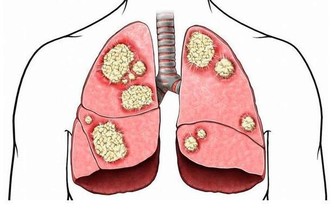

病理性小便分叉是由疾患引起的,除前列腺增生外,其他疾病如急性尿道炎或急性前列腺炎,由於尿道充血、腫脹,分泌物增多,也會導緻小便分叉。